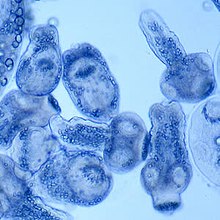

O Echinococcus sp, por exemplo, fica no intestino.

Dioctophyma renale é um parasita no rim dos cães.